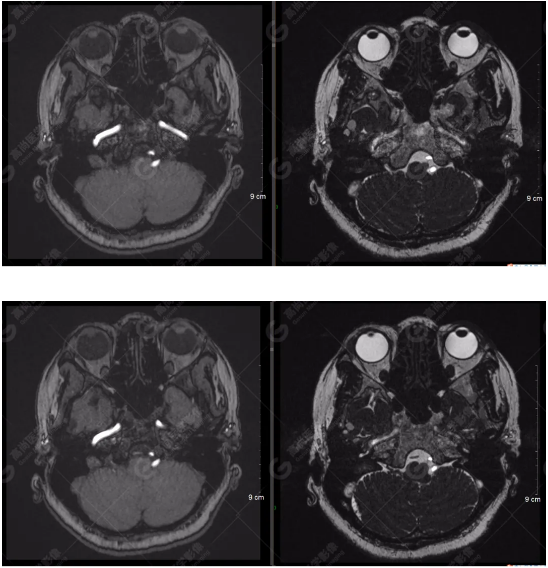

顱腦MRA及ciss序列示腦基底動(dòng)脈環(huán)完整,雙側(cè)頸內(nèi)動(dòng)脈末段、大腦前動(dòng)脈、大腦中動(dòng)脈、大腦后動(dòng)脈及其主要分支顯影良好,管徑及走行正常,無明顯局灶性增粗或變細(xì)。雙側(cè)椎動(dòng)脈末段沿延髓左側(cè)向上走行,左側(cè)面聽神經(jīng)輕度受壓移位,左側(cè)面聽神經(jīng)周圍見細(xì)小血管包繞。右側(cè)面聽神經(jīng)及雙側(cè)三叉神經(jīng)周圍未見異常血管影。

1.雙側(cè)椎動(dòng)脈末段沿延髓左側(cè)向上走行,左側(cè)面聽神經(jīng)輕度受壓移位,左側(cè)面聽神經(jīng)周圍見細(xì)小血管包繞,可符合面聽神經(jīng)壓迫綜合征。